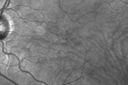

63-year-old woman has juxtafoveal retinal telangiectasis in both eyes. She notices her vision a little worse with more distortion and change over the last six months.

VISUAL ACUITY: OD 20/40, OS 20/40. IOP: OD 11, OS 12. The posterior chamber intraocular lens is in good position in both eyes.

FUNDUS PHOTOGRAPHY - AUTO FLUORESCENCE: The image in the right eye does show hypo auto fluorescence in the center of the fovea from the lack of normal pigment deposition, which is common in patients with juxtafoveal retinal telangiectasis.

SPECTRALIS-SD-OCT SCAN: The OCT scans both show foveal gaps in the retina.

1. JUXTAFOVEAL RETINAL TELANGIECTASIS – BOTH EYES (MACULAR TELANGIECTASIA)

DISCUSSION: I explained to the patient her retina problem unfortunately is at the moment untreatable, but generally doesn’t cause substantial vision loss in both eyes. Some people do develop neovascularization.